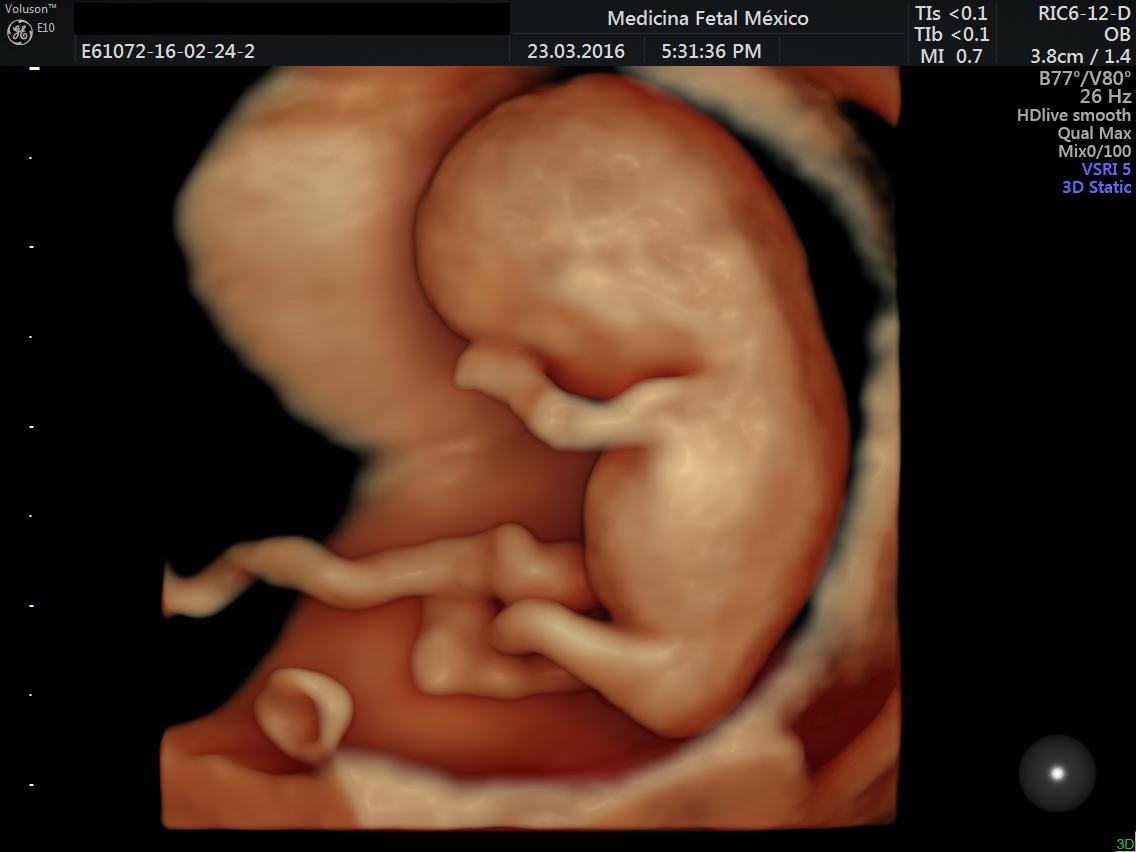

En Medicina Fetal México estamos siempre a la vanguardia en tecnología

Contando con los mejores equipos de ultrasonido de alta Resolución, para que junto con nuestros especialistas se brinde el Un diagnostico preciso y puedas disfrutar con tranquilidad tu embarazo.

- 2 equipos Voluson E10